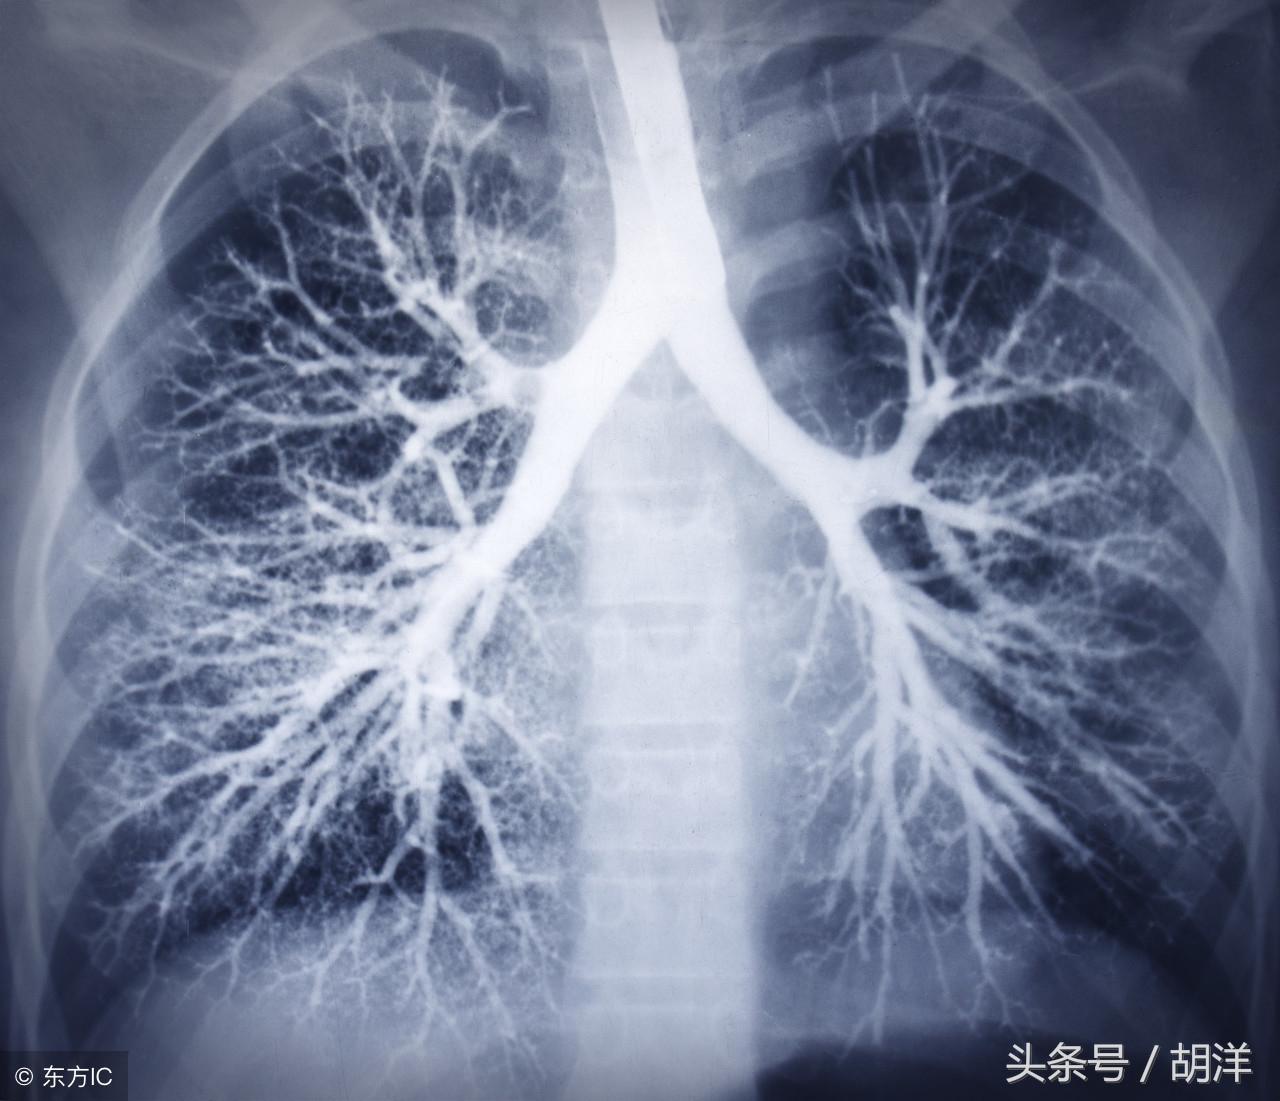

咳血又称咯血,是呼吸科一个比较严重的症状,由于其可能提示肺部肿瘤等严重疾病而受到重视,但事实上在引起咯血的病因中,肺部恶性肿瘤所占的比例并不是很大,但很多人因咯血而焦虑异常,特别是咯血久治不愈情况下,更加令人无法正常的生活和学习,那么哪些疾病可能导致反复发作痰中带血或者咳出满口鲜血呢?

支气管扩张

支气管扩张是一种支气管管壁结构破坏性疾病,正常情况下,支气管是一个带有弹性,拥有一定管径的能够维持正常呼吸通气的结构,当管壁结构受到破坏时,气管会受到被动的牵拉而扩张,管壁的血管由于弹性较小,容易被撕扯呈血管瘤改变,一旦胸腔内血流压力增大可能冲破血管瘤变薄的管壁而导致大咯血,少量渗血时则呈现为痰中带血。